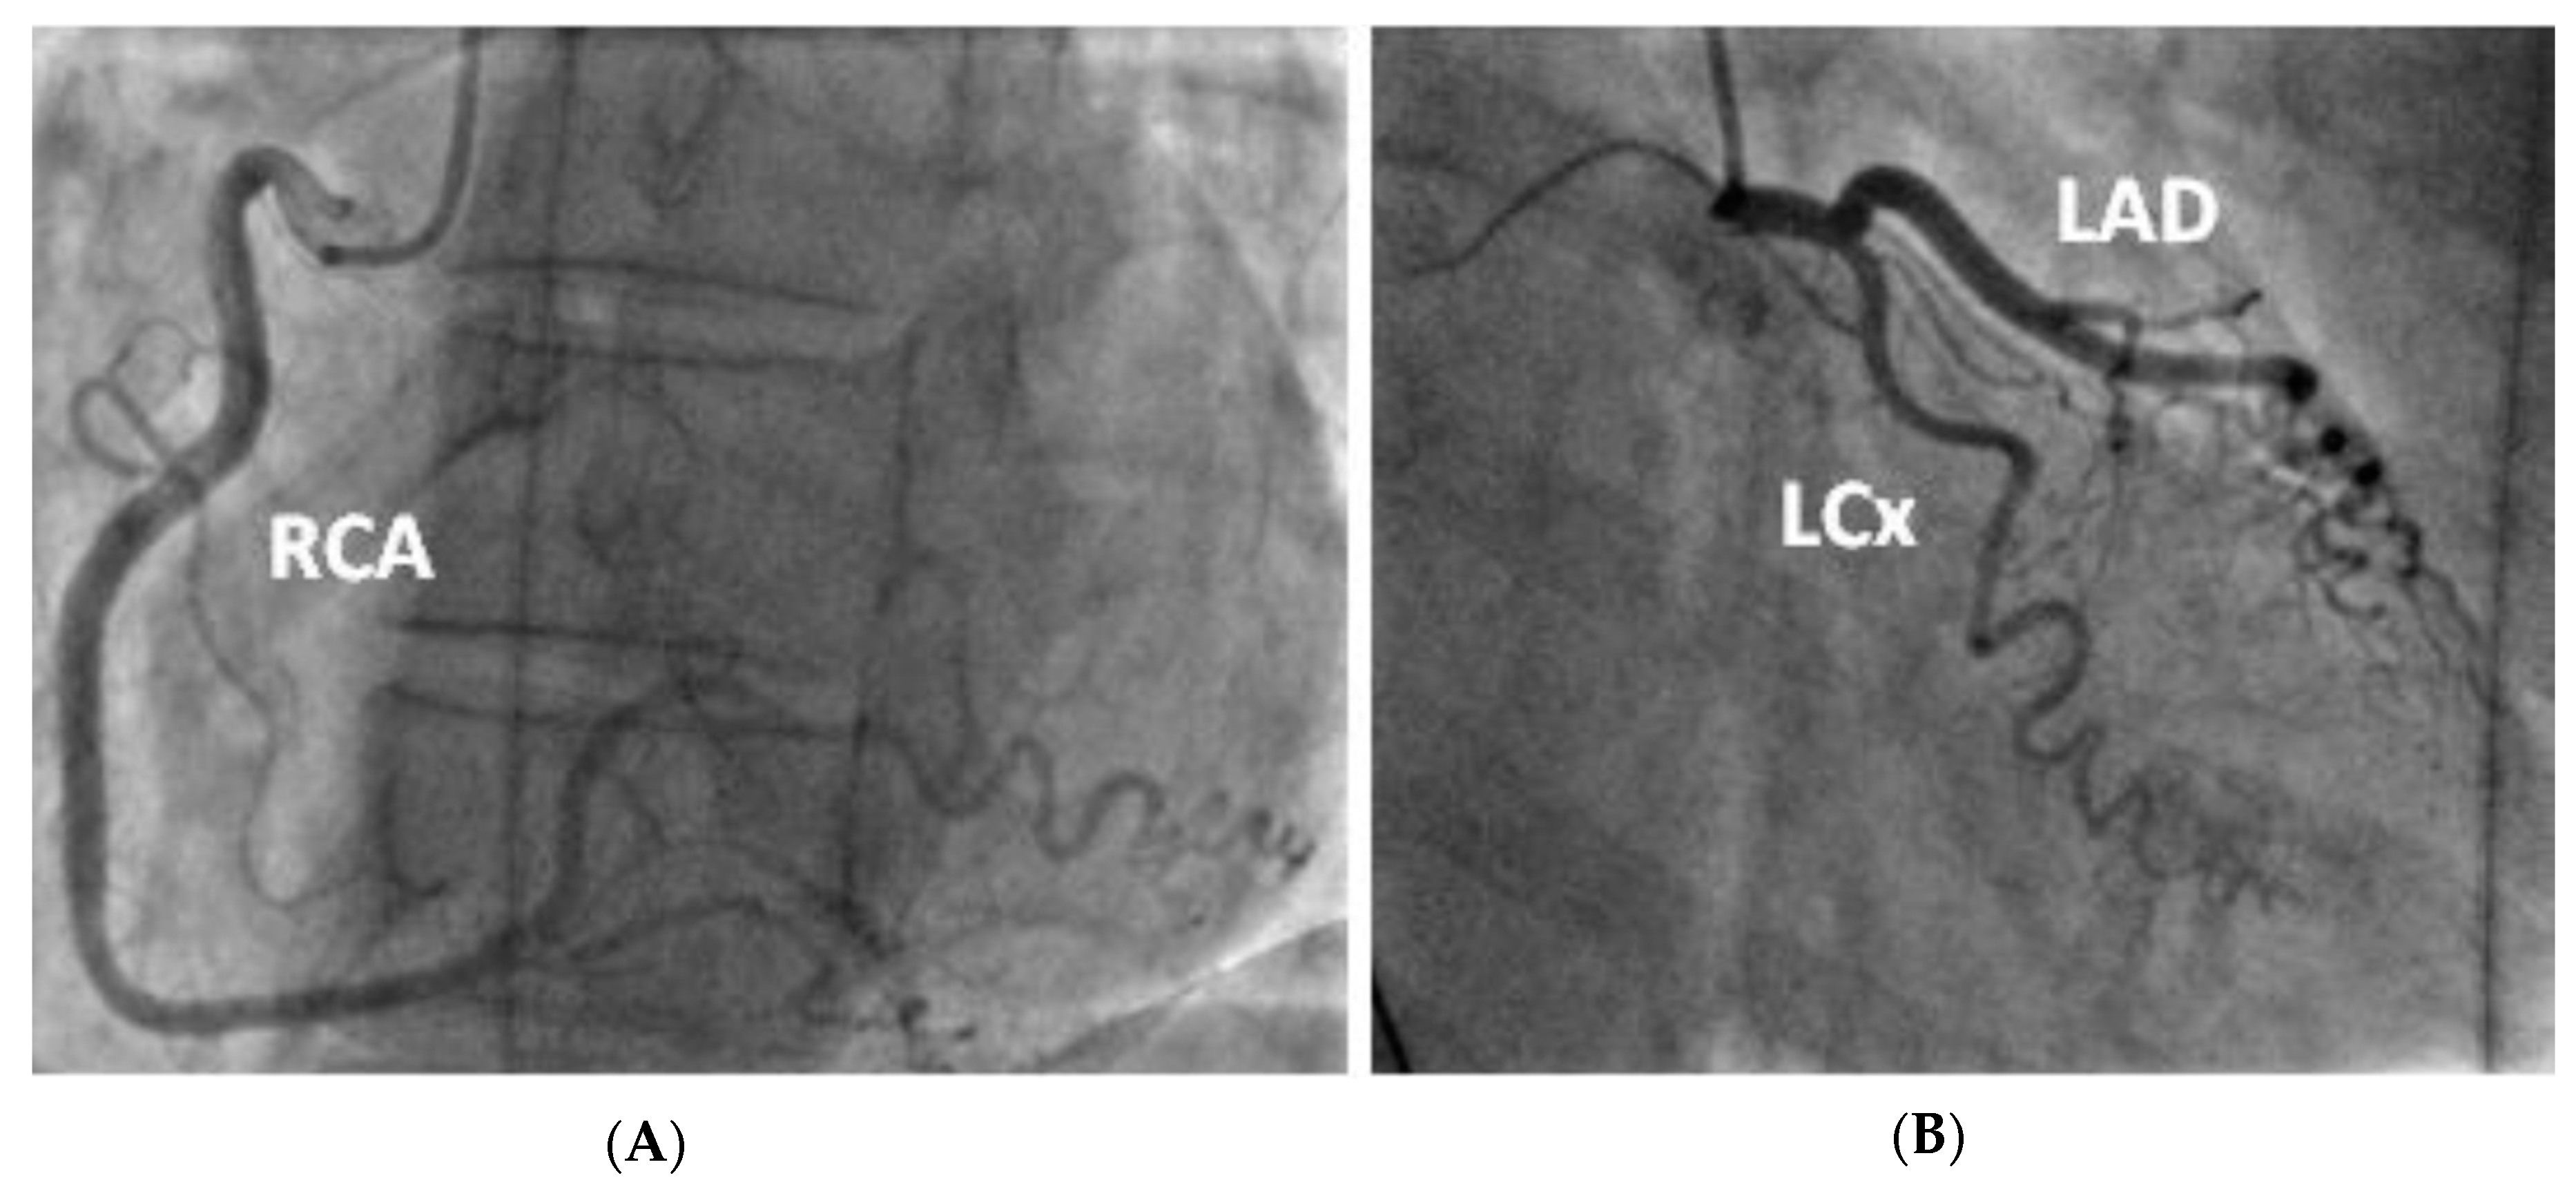

Figure 3.

Coronary angiogram demonstrating tortuous unobstructed coronaries. —(A) LAO straight view of the right coronary artery after injection of contrast (B) RAO caudal view of the left coronary artery (including the left main stem, left anterior descending and left circumflex artery).